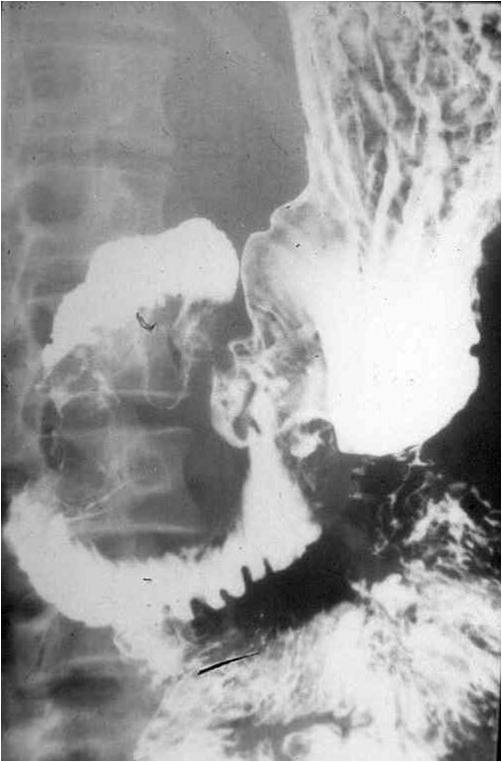

Image

Fig.26.: Napkin ring sign (or apple core sign), is a typical presentation of colon tumors.

Fig.27. Rectal cancer arising from a villous adenoma causes a rugged contour and an extensive filling defect.